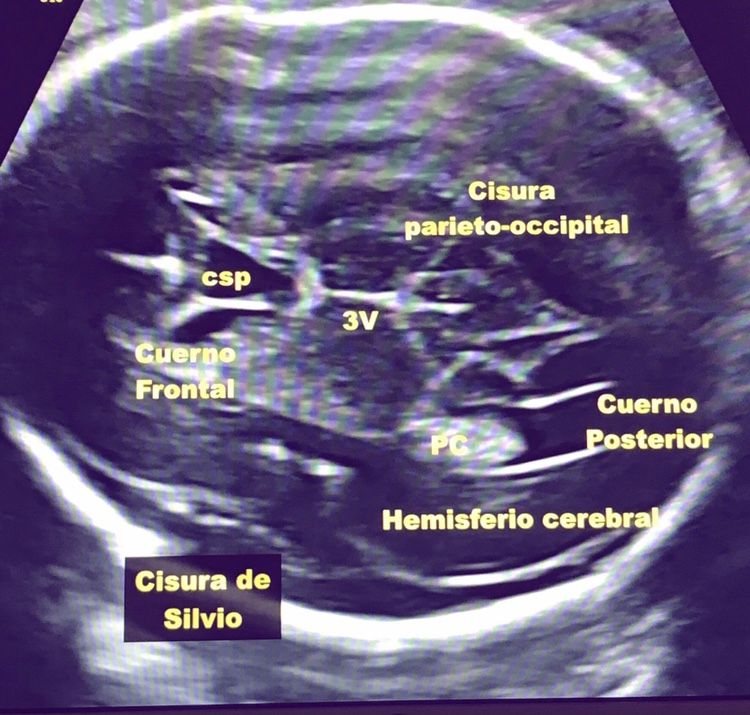

Ultrasonido estructural del segundo trimestre

Recomiendo ampliamente a la doctora por la excelente atención que recibí. Desde el inicio fue muy amable, dedicada y profesional, lo que me hizo sentir tranquila y en confianza en todo momento. Durante la ecografía me fue explicando con paciencia cada parte del cuerpo de mi bebé, resolviendo todas mis dudas y haciendo de la experiencia algo muy especial. Me encantó poder verlo bien y sentir que estaba en buenas manos. Sin duda, una atención de calidad que se agradece muchísimo.

• Dra. Issumi A. Meza Meneses • Ultrasonido estructural del segundo trimestre •